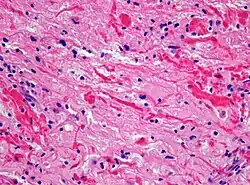

Makroskopisch handelt es sich um knollige, derbe Tumoren mit grau-weißer Schnittfläche, oft mit zystischen Anteilen. Feingeweblich handelt es sich um astrozytäre Tumoren, deren Tumorzellen charakteristische feine bipolare fibrilläre Fortsätze ausbilden und (namensgebend für den Tumor) als Pilozyten (Haarzellen) bezeichnet werden. Die mitotische Aktivität ist niedrig. Charakteristisch ist die relativ scharfe Abgrenzung gegenüber dem umgebenden Hirngewebe sowie ein biphasisches Wachstumsmuster, wobei sich faserreiche Abschnitte mit zahlreichen Rosenthal-Fasern und faserarme mikrozystisch aufgelockerte Bereiche mit sogenannten eosinophilen granulären Körpern abwechseln.